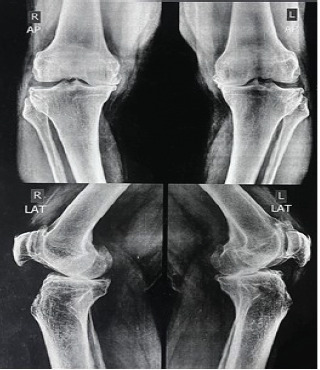

Polyethylene Insert Wear Leading to Early Aseptic Bilateral Total Knee Arthroplasty Failure: Case Report

Vishwajit Patil , Neeraj Adkar , Mangesh Patil , Ravi Kerhalkar , Prajwal Sadlagi , Narendra Nagle

………………………………p.217-222